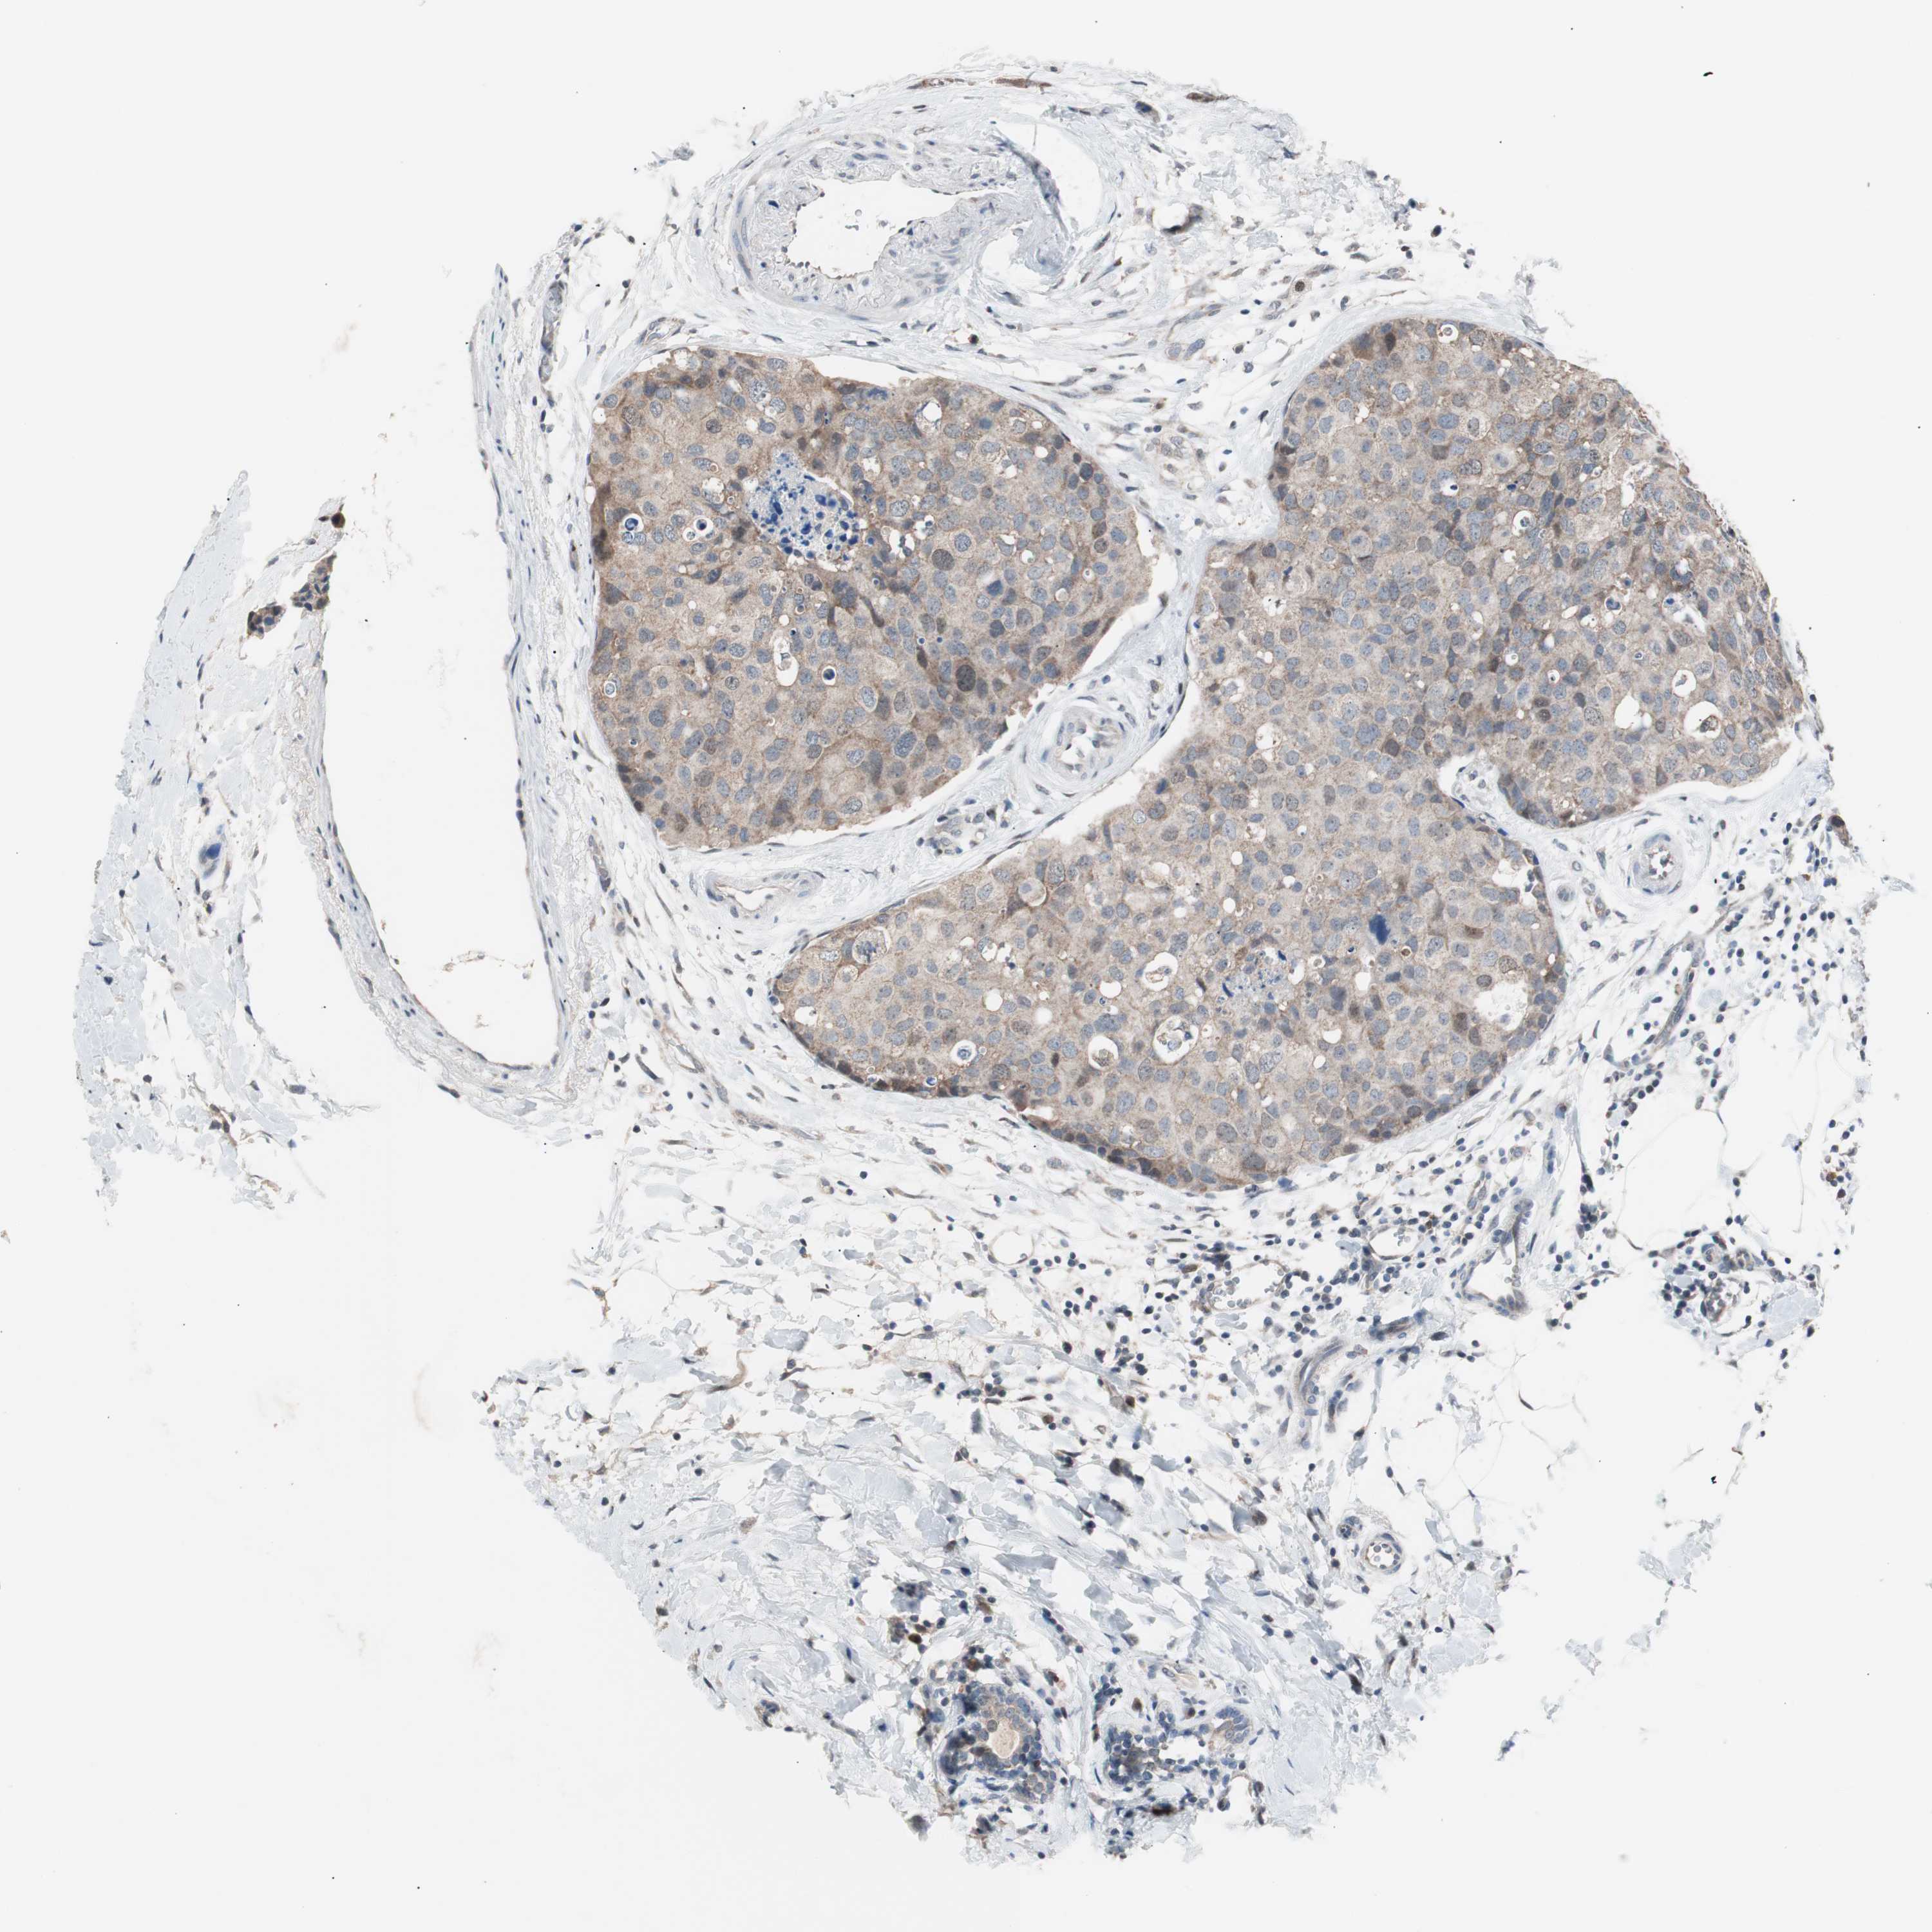

BRCA TCGA BRCA VALIDATION PROTEIN EXPRESSION

ANTIBODIES

AND

VALIDATION